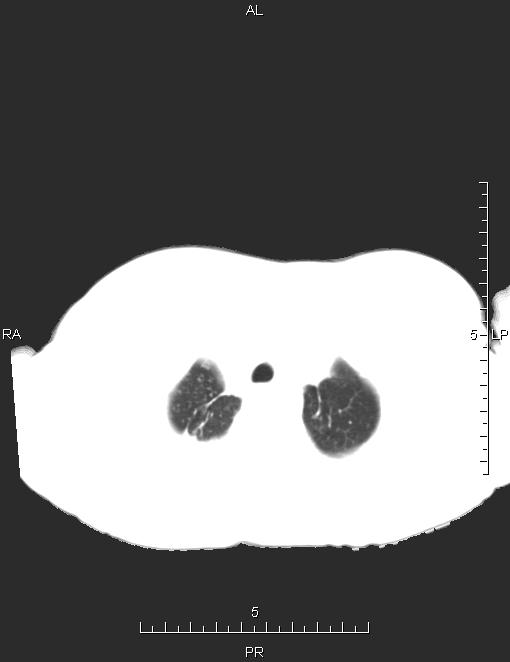

CT49620:胸部CT

女,73岁,咳嗽、咳痰、发热2天。

双肺上野TB 左心功能不全并肺动脉高压肺淤血

双上肺陈旧性肺结核,慢性支气管炎

双肺上叶陈旧性病灶。

慢支伴感染,双肺上叶陈旧性病灶。

慢阻肺并感染,双上陈旧性肺结核